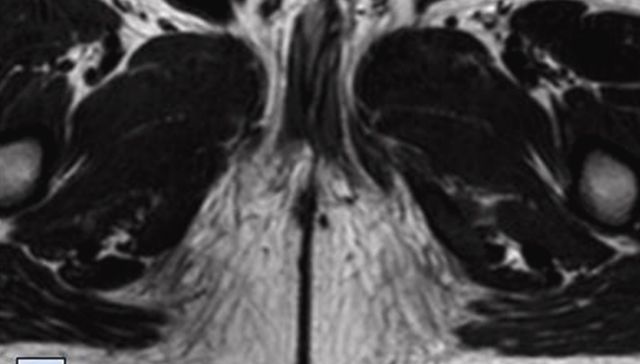

La médula ósea está implicada en el desarrollo de la aterosclerosis